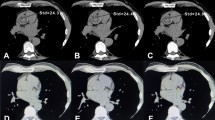

All patients sequentially underwent a standard non-contrast enhanced CT scan (tube voltage 120 kVp, 25 mAs, pitch 1.2, rotation time 2.1 ms, Matrix 128 × 128, collimation 1.6 × 1.2) and a low-dose CT acquisition (tube voltage 80 kVp, 20 mAs, pitch 1.2, rotation time 0.6 ms, Matrix 128 × 128, collimation 1.6 × 1.2). Standard scans were performed in cranio-caudal direction during inspiratory breath-hold with prospective electrocardiogram (ECG)-triggering. Low-dose scans were performed also in cranio-caudal direction, but without breathing instruction and without electrocardiogram (ECG)-triggering. All post-acquisition processing and reconstruction were done in a similar fashion for both the low and standard dose scans. Radiation Dose was approximately 0.6 mSv for the standard protocol and 0.2 to 0.3 mSv for the low-dose protocol.

All images were read in consensus by a board-certified nuclear medicine physician and a board-certified cardiologist.

Calcium scoring was done, equally for the 80 and 120 kVp acquisitions using a dedicated semiautomatic software included in Syngo.Via workstations (Siemens Healthineers AG, Erlangen, Germany). In brief, all pixels with an attenuation equal or above the lowest threshold (i.e., ≥ 130 HU) having an area ≥ 1 mm2 are automatically color-marked and then manually selected by creating a region of interest around all lesions found in a coronary artery. The software then calculates the CACS as previously reported,9 by multiplying the density score and the area of calcification.

Overall, there was a very good correlation between scores calculated with 120 and 80 kVp tube voltage scans (R = 0.94, R2 = 0.88, P > .001). Bland–Altman limits of agreement of − 563.5 to 871.9 and a bias of − 154.2 (Figures 1, 2).